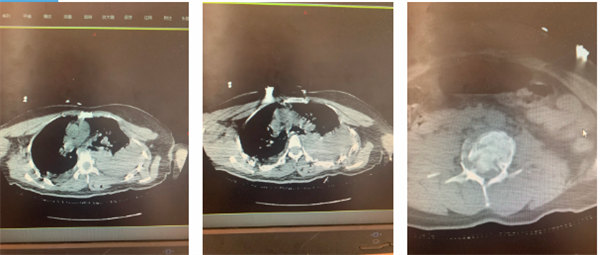

術(shù)前影像

骨一科團隊檢查后發(fā)現(xiàn),患者腰椎爆裂性骨折 、胸椎爆裂性骨折、腰脊髓損傷伴下肢癱瘓、胸腰椎多發(fā)橫突骨折、胸腰椎多發(fā)棘突骨折、左側(cè)肩胛骨骨折、閉合性胸部損傷、肋骨多處骨折、胸骨骨折……按照常規(guī)治療流程,應(yīng)于患者受傷后6至8小時行急診手術(shù)減壓、內(nèi)固定,解除神經(jīng)壓迫,重建脊柱穩(wěn)定性。但由于患者一方面失血過多導(dǎo)致血壓不穩(wěn)定;另一方面左側(cè)胸壁塌陷,雙側(cè)多處肋骨骨折,且腹部情況未完全查清;再者患者腰椎手術(shù)需俯臥位進行,手術(shù)體位或加重胸部損傷。同時多學(xué)科會診發(fā)現(xiàn)患者伴有嚴(yán)重創(chuàng)傷性血氣胸、創(chuàng)傷性濕肺、閉合性腹部損傷。